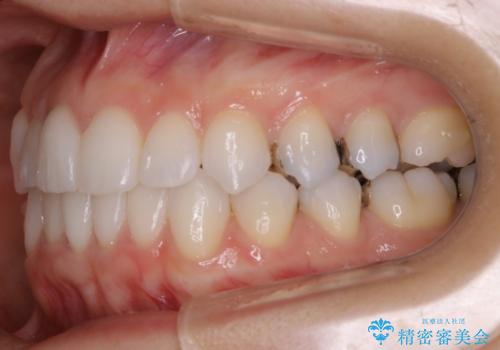

- 前歯のガタつき改善を主訴にご来院されました。

ガタつき自体は軽度で、奥歯の噛み合わせのズレもほとんどなかったため、非抜歯でマウスピース矯正装置を選択しました。

歯列の幅の拡大と歯を小さくする調整を行うことで並べるスペースの確保を行いました。この方法は、ガタつきをとりたいところに直接スペースを作ることができるので治療期間を短縮することができ効率的です。